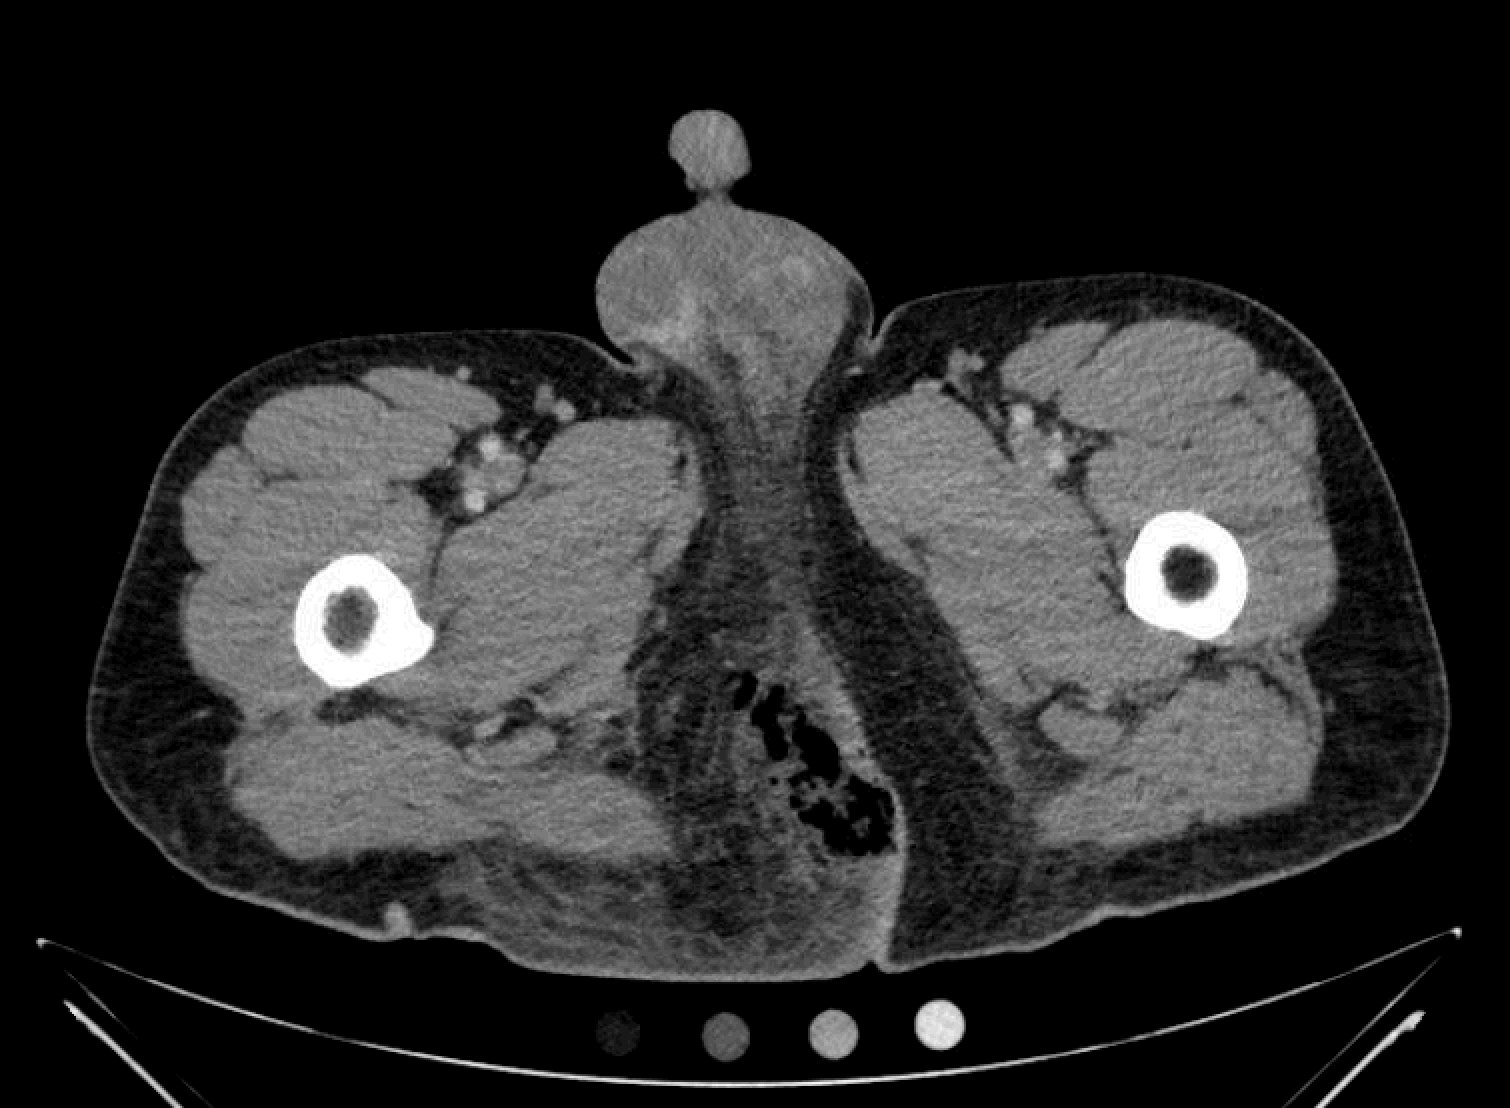

The computed tomography (CT) of the abdomen and pelvis revealed significant subcutaneous gas tracking along the perineum and right gluteal region (orange outline) into the scrotum with associated scrotal edema (yellow arrow) and subcutaneous inflammatory fat stranding of 0.92 cm (red arrow) consistent with Fournier’s gangrene. There is early fluid loculation along the right medial gluteal cleft of 5.85 cm (green arrow) without a sizeable drainable abscess seen.